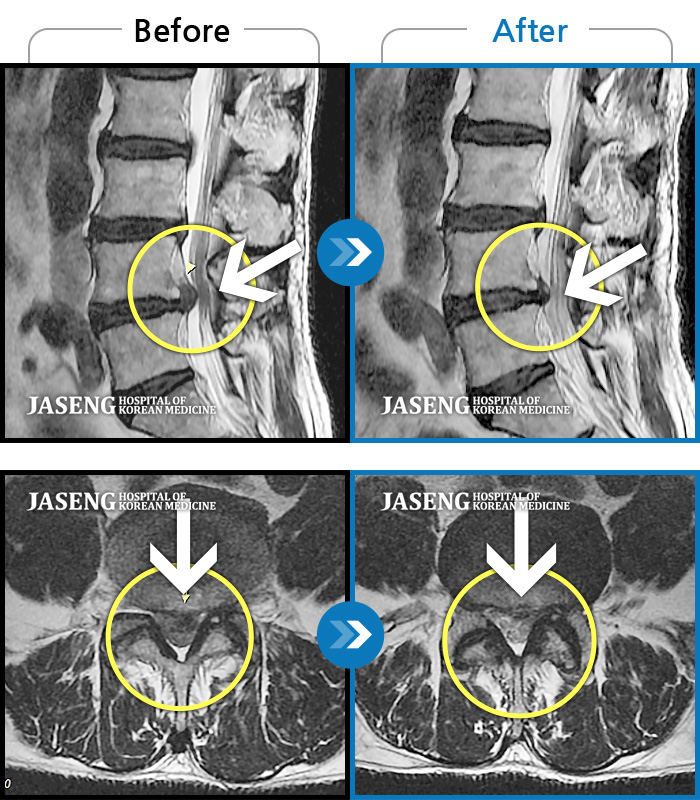

MRI 치료사례

허리디스크로 옆으로 쪼그려 누워서 내원